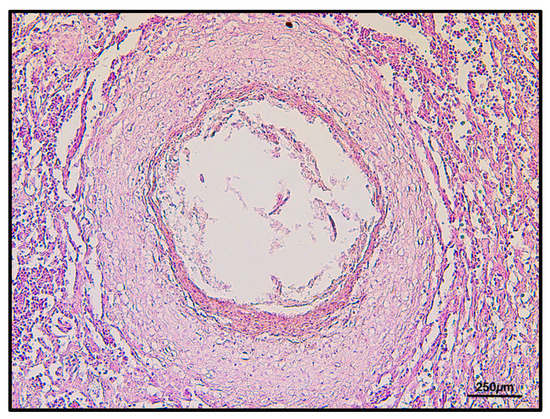

By histology, several nematodes encysted through the gastric wall were found in both sub-serosa and sub-mucosa (Figure 3). Frequently, parasitic bodies were surrounded by a thick granulomatous reaction, made up of macrophages, epithelioid cells, some lymphocytes and an external connective sheet, although singular parasites appeared to be simply encysted within a thin fibrous reactive capsule.

Figure 3. Mucosal granulomatous reaction with nematodes inside, H&E 2.5×.